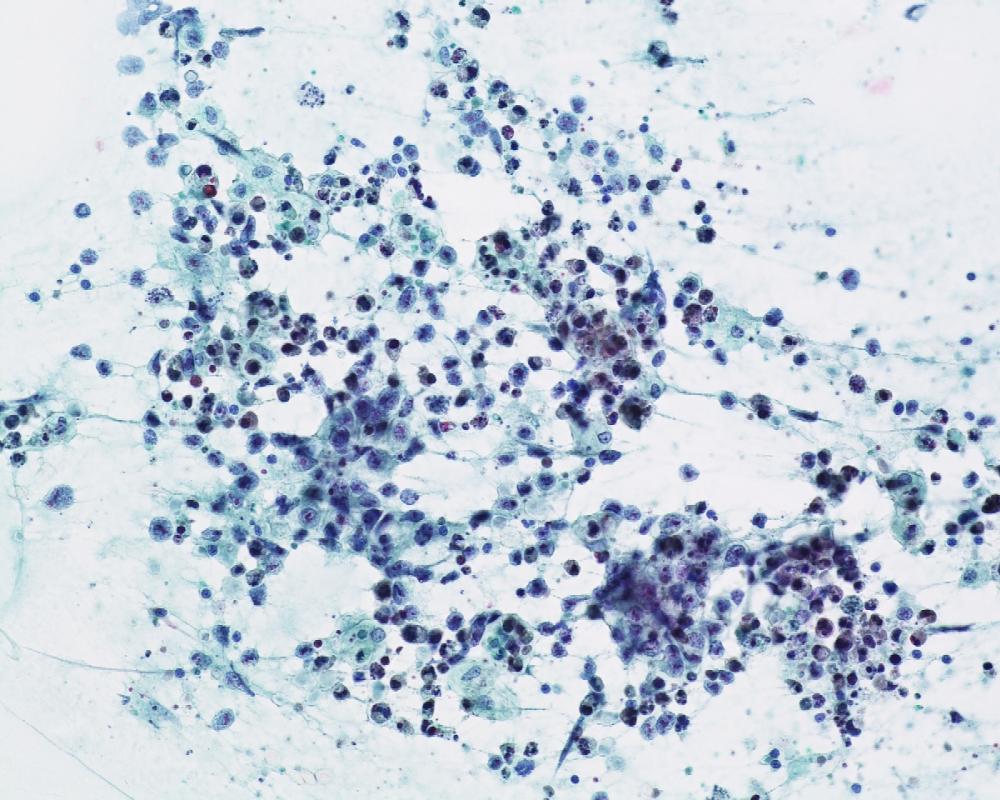

第40回日本臨床細胞学会九州連合会学会(大分)スライドカンファレンス症例3

種別:泌尿器

出題:橋向 圭介 熊本大学病院病理部

| 年齢 | 70代 | 性別 | 男性 |

| 採取部位 | 分腎尿 | 採取方法 | カテーテル |

| 検体処理法 | 2回遠心法(YM式液状検体固定液) |

既往歴:胸椎多発性骨髄腫治療中

現病歴:2021年より胸椎多発性骨髄腫の化学療法中であり、治験前スクリーニングの単純CT検査にて左尿管軟部影を指摘。同時期に腰痛、水腎症が出現し、精査目的のため分腎尿が提出された。

| 正解 | 5.形質細胞腫 |

▼選択肢及び投票結果

| 1.ウイルス感染細胞 | 21件 | (20.0%) | |

| 2.低異型度尿路上皮癌 | 8件 | (7.6%) | |

| 3.高異型度尿路上皮癌 | 30件 | (28.6%) | |

| 4.小細胞癌 | 3件 | (2.9%) | |

| 5.形質細胞腫 | 43件 | (41.0%) | |

| 投票総数 | 105件 | (100%) |